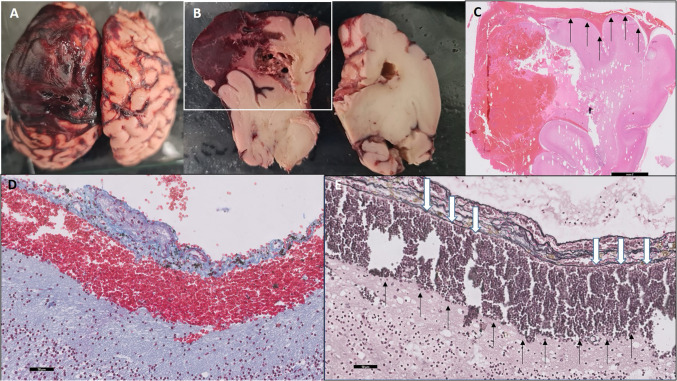

脑膜下出血是一种罕见的颅内出血,通常发生在新生儿身上。我们报告了一名28岁初产妇的首次产前诊断,胎儿磁共振成像(MRI)通过其特征皮质向内凹陷(“皮质屈曲”)和表观扩散系数图上的扩散受限来确定其脑膜下出血,后来通过尸检证实。本病例提示腹膜下出血的发病机制是胎儿的内在因素,而不是出生创伤或新生儿窒息,并强调了胎儿MRI在区分腹膜下出血和其他胎儿出血方面的关键作用,对产前咨询和围产期管理具有重要意义。

Subpial hemorrhage is a rare intracranial hemorrhage typically described in neonates. We report the first prenatal diagnosis of subpial hemorrhage in a 28-year-old primigravida, defined on fetal magnetic resonance imaging (MRI) by its hallmark cortical inward depression ("cortical buckling") and restricted diffusion on the apparent diffusion coefficient map, and later confirmed by autopsy. This case implicates intrinsic fetal factors-rather than birth trauma or neonatal asphyxia-in subpial hemorrhage pathogenesis and highlights the critical role of fetal MRI in distinguishing subpial hemorrhage from other fetal hemorrhages, with important implications for prenatal counseling and perinatal management.